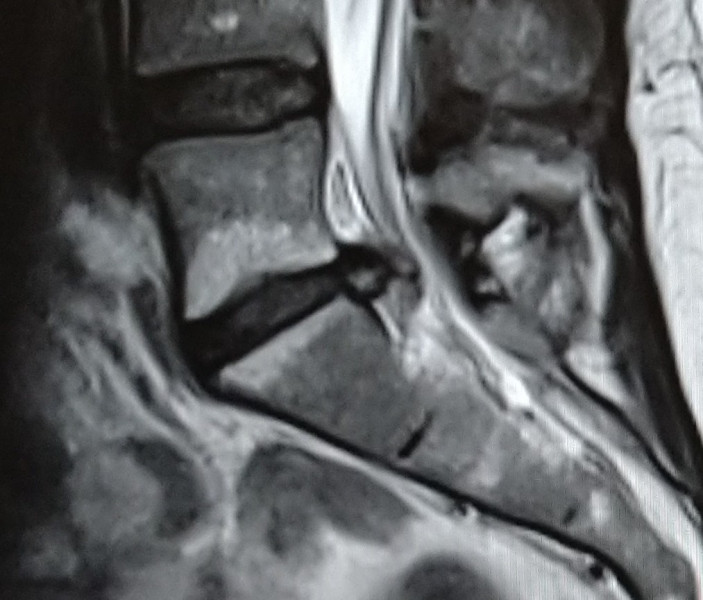

ChristmasPuddingAllRound · 30/04/2022 11:01

I've added part of the MRI just in case anyone is good at reading them...

Could this be cauda equina

OP posts: